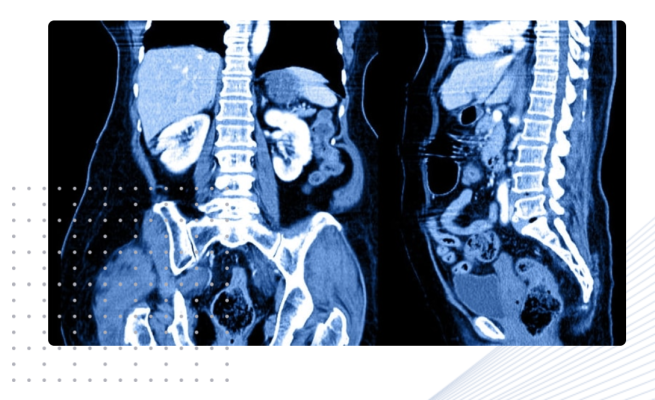

April 29, 2022 — Nano-X Imaging LTD, an innovative medical imaging technology company, today announced that its deep-learning medical imaging analytics subsidiary, Nanox.AI, received FDA 510(k) clearance for HealthOST device, an AI software that provides qualitative and quantitative analysis of the spine from CT to support clinicians in the evaluation and assessment of musculoskeletal disease. Measurements of vertebral fractures and low bone density have been shown to increase the identification of patients with musculoskeletal disease of the spine, such as osteoporosis, a disease that affects more than 10 million people in the U.S.1

This is Nanox.AI’s tenth FDA clearance across its innovative portfolio of AI clinical decision assist tools and second FDA clearance for its vertebral compression fracture device. HealthOST offers a more detailed evaluation, including the ability to measure fractures more precisely, potentially aiding clinicians in evaluating risk factors for osteoporosis. The company’s latest AI solution automatically identifies findings suggestive of compression fractures and low bone density, enabling further work up and treatment of patients diagnosed with osteoporosis to prevent potentially life-changing major osteoporotic fractures, such as a hip fracture. Nanox.AI previously received FDA clearance in May 2020 for the AI software that identifies vertebral compression fractures.

HealthOST provides qualitative and quantitative analysis of the spine, including labeling of T1-L4 vertebrae, measurement of height loss in each vertebra (T1-L4) and measurement of the mean Hounsfield Units (HU) in volume of interest within vertebra (T11-L4). HealthOST is indicated for use in patients aged 50 and over undergoing CT scan for any clinical indication that includes at least four vertebrae in the T1-L4 portion of the spine (for vertebral height loss) and T11-L4 (for bone attenuation) portions of the spine.